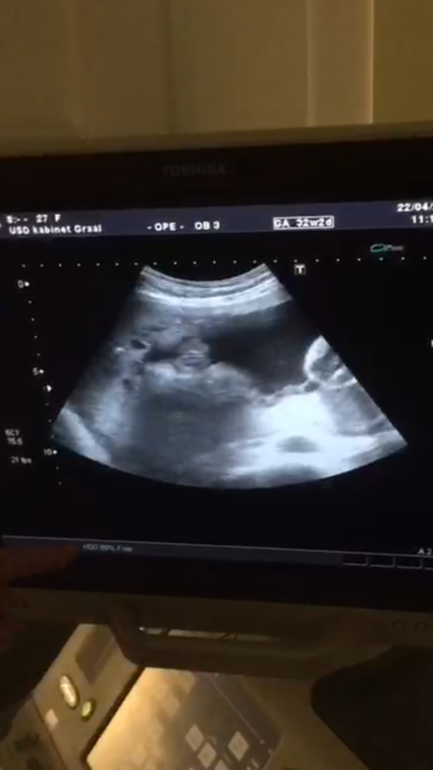

Результаты: УЗИ, КТГ, доплера, скринингаУра ура ура 3 скрининг пройден! Весим мы 2050, срок по менструации 32,2 по УЗИ 33,1, ПДР 9 июня, итого осталось ходить ещё 7 недель 😅 Ну и девочку ещё раз подтвердили и показали )) расскажите сколько ваши малыши весили на таком сроке?

У моей головушка сейчас 305 вроде нормальная судя по таблицам ) животик 290